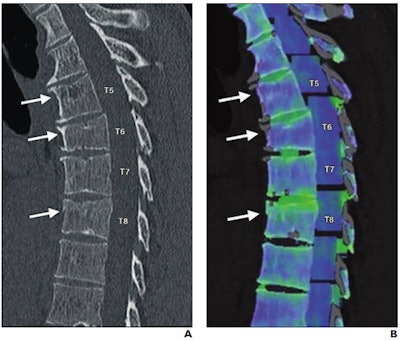

There's been debate about DECT's value in clinical use, Wong and colleagues noted. They conducted a study to investigate the technique's effect on radiologists' reports and thus on patient care. The research included reports from 3,159 CT exams performed in the emergency department in 2016; these exams were categorized into five categories: head and neck, chest, abdomen and pelvis, spine, and musculoskeletal.

Of the 3,159 exams, dual-energy CT was not mentioned in the report in most cases (71.9%). But in those cases that did make use of the technique, dual-energy CT potentially altered clinical management in 9.4%, increased diagnostic confidence in 14.4%, offered relevant new information in 5.6%, and helped characterize incidental findings in 1.4% of cases. Dual-energy CT altered patient management most in the musculoskeletal category, at 89%; of these, 70% of the exams were performed to confirm gout.